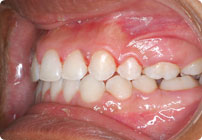

Despues

Caso: 11 años

Adolescente: Clase II

Mordida Cruzada Posterior

Sin extracción

Sin uso de expansores

6 alambres superiores

5 alambres inferiores

Sin uso de elásticos

Retenedores: Interior Fijo de TMA y Hawley en superior

Tiempo de tratamiento: 14 Visitas